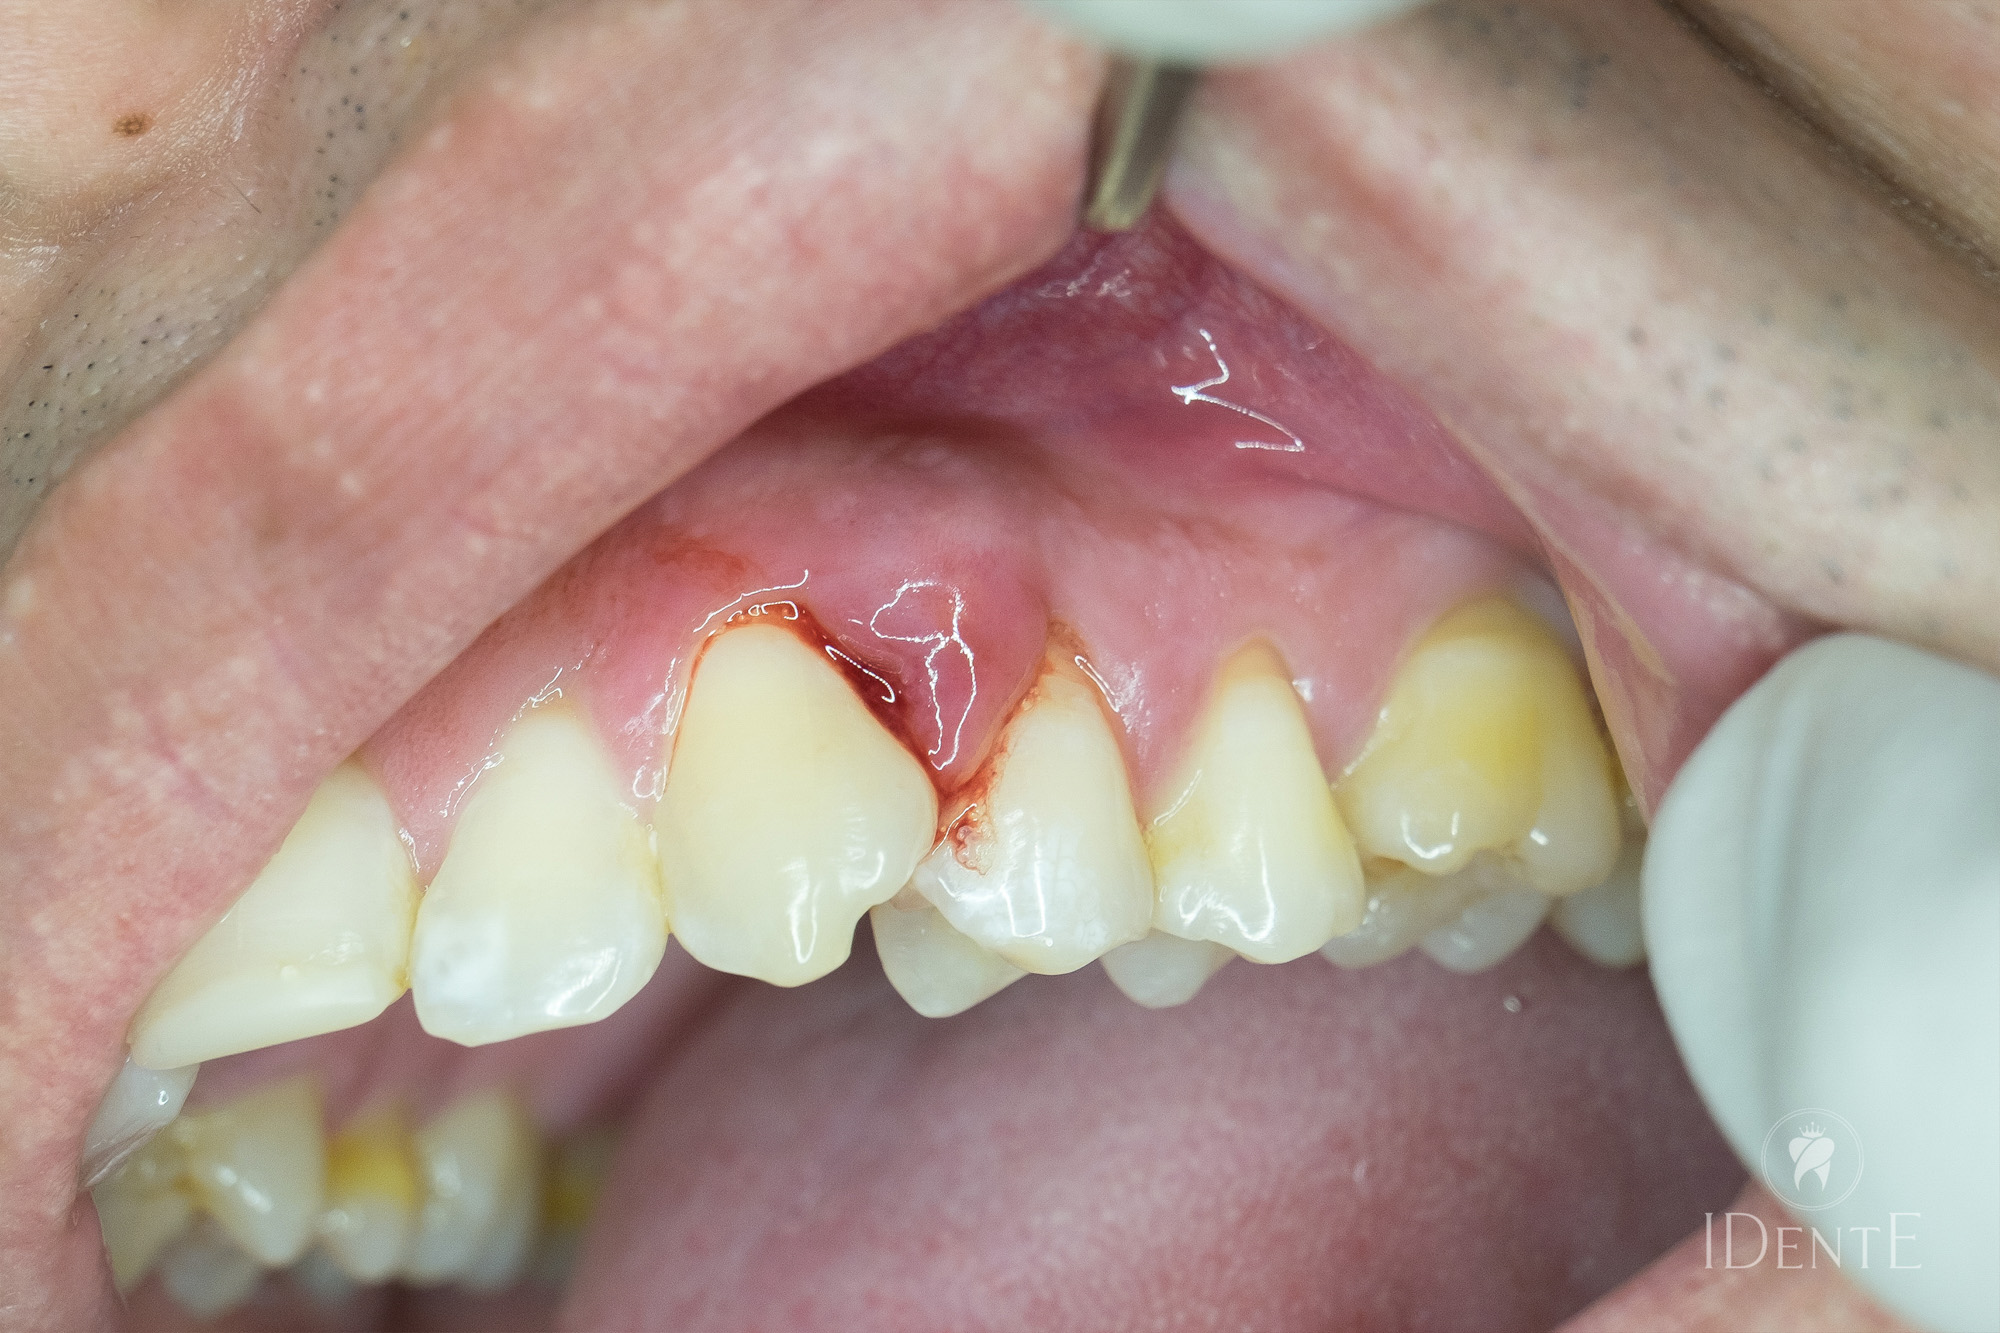

Parodontološki žepki so eden izmed najpogostejših znamenj napredovanega vnetja dlesni in parodontalnih struktur, ki lahko vodijo v izgubo obzobnih vezi in kostnih struktur. Gre za globoke “žepke”, ki se tvorijo med zobmi in dlesnijo, ko bakterijski plak in zobni kamen prodreta pod nivo dlesni ter sprožita kronično vnetje. Zdravljenje z luščenjem in glajenjem korenin (scaling and root planing – SRP) je široko priznana, neinvazivna terapija prve izbire za nadzor in zaustavitev napredovanja parodontalne bolezni.

Parodontološki žepki nastanejo, ko se dlesen zaradi kroničnega vnetja odmakne od zoba, sledi ločitev vezi in izguba kosti okrog zobnega korena. Te globoke subgingivalne “žepke” napolni bakterijski plak, ki ga običajno z navadnim ščetkanjem ni mogoče učinkovito odstraniti. Nezdravljeni žepki predstavljajo rezervoar bakterij, ki sprožajo nadaljnje vnetje in kostiogeno razgradnjo.

Če globina žepkov presega 4 mm in kaže znake vnetja (krvavenje, oteklina), je luščenje in glajenje korenin priporočljivo kot prva neinvazivna terapija. Cilj je odstraniti bakterijska žarišča, preprečiti nadaljnjo izgubo vezi in kostno razgradnjo ter izboljšati samopodobo bolnika.